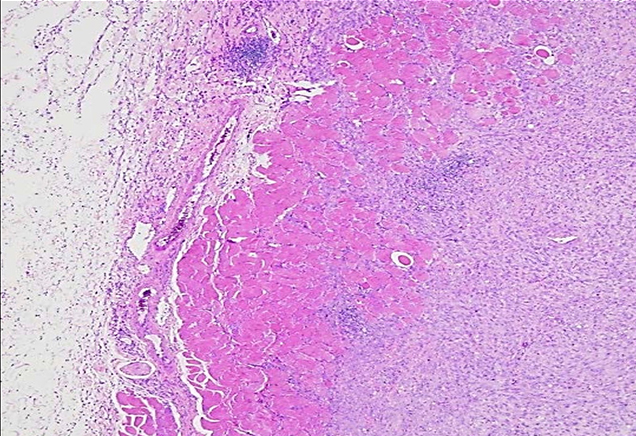

肿瘤检体经过病理染色与医师判读后,确定肿瘤的类型、分级与分期,拟出适合的治疗方案与用药组合。

· 实验室人员进行标准病理染色程序